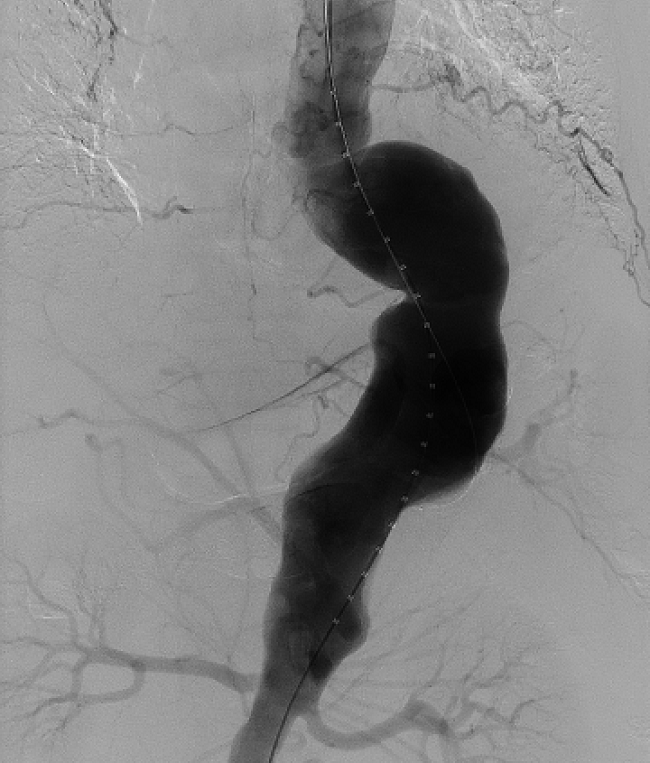

▲ “胸腹主动脉瘤覆膜支架内脏四分支开窗腔内隔绝术”示意图

副院长王兵教授详细了解患者病情,在与家属充分沟通后,决定为杨先生实施胸腹主动脉瘤覆膜支架内脏四分支开窗腔内隔绝术。由于这种复杂腔内修复技术需要术前充分评估、精确测量定位、技术难度高,目前能开展此类高难度手术的医院很少,经王兵教授耐心细致的讲解,终于使杨先生和家属的焦虑心情如释重负,欣然接受并期盼早日手术,拆除体内不定时“炸弹”。